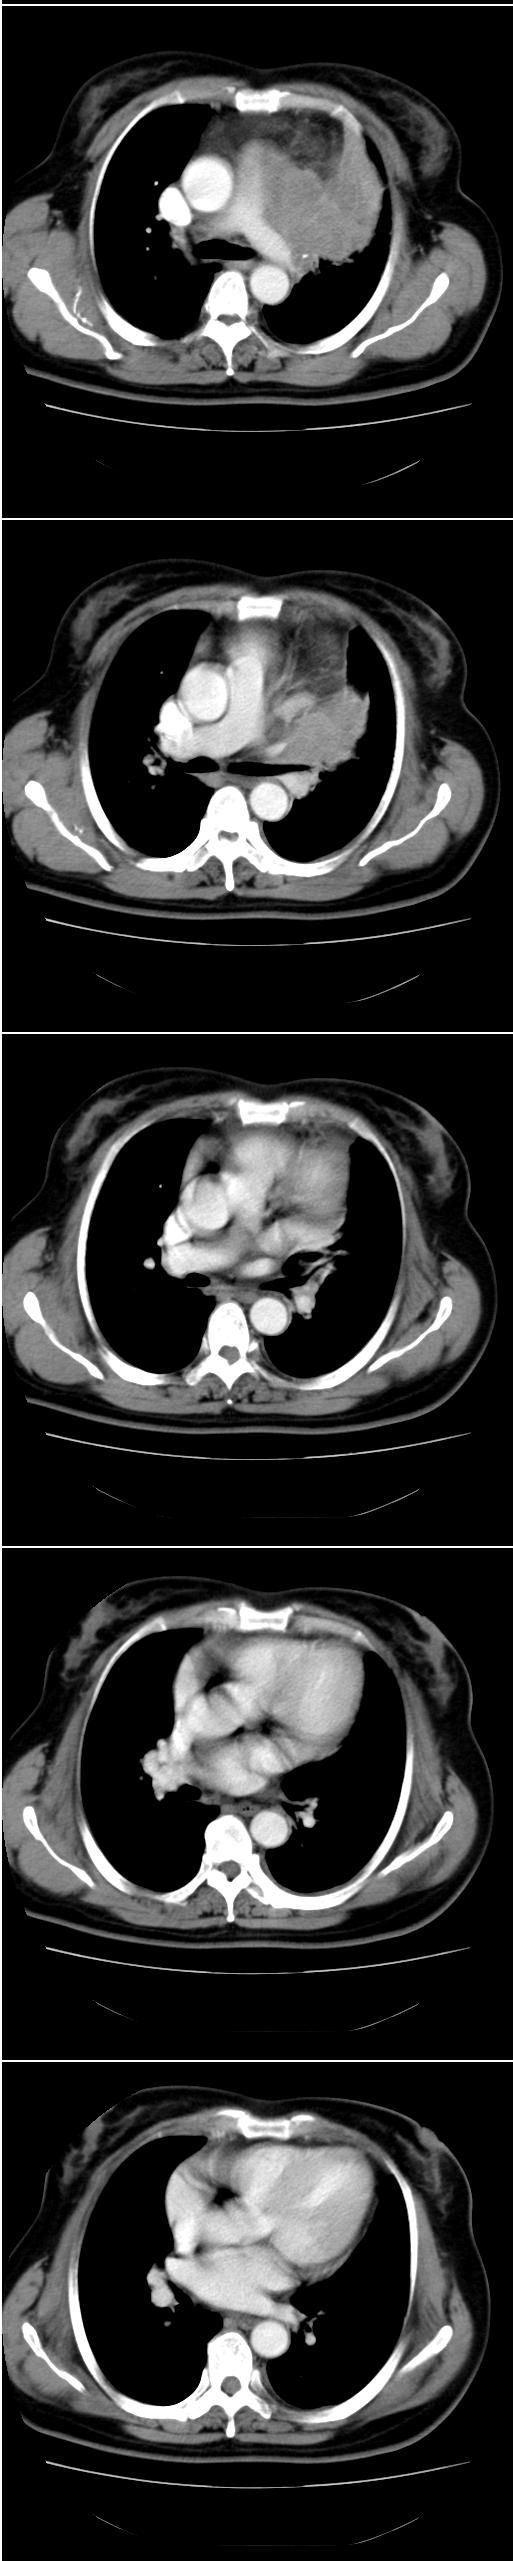

标题: CT13028:女,56岁。咳嗽、气促一月,咳血一周。CT值增加约30 [打印本页]

标题: CT13028:女,56岁。咳嗽、气促一月,咳血一周。CT值增加约30

考虑左上肺癌(周围型)伴左肺门及纵隔转移(主肺动脉窗旁病灶可能为肿大并坏死的淋巴结),不除外纵隔型肺癌

软组织肿块,应该有肺不张(因为左膈及脾脏\\胃抬高明显):考虑中央ca

支持纵隔旁型肺癌伴主动脉弓\\主肺动脉及左侧头壁动脉受侵.

考虑左肺中心性肺癌并纵隔淋巴结转移,累及左肺动脉及左侧头臂静脉.但不除外纵隔恶性肿瘤累及肺组织.

考虑左侧中央型肺癌伴左肺上叶肺不张及前纵隔淋巴转移。

1)考虑为:左肺上叶中心型肺癌伴左肺上叶阻塞性肺炎、节段性肺不张,左肺门及纵隔淋巴结转移。2)左侧少量胸腔积液。